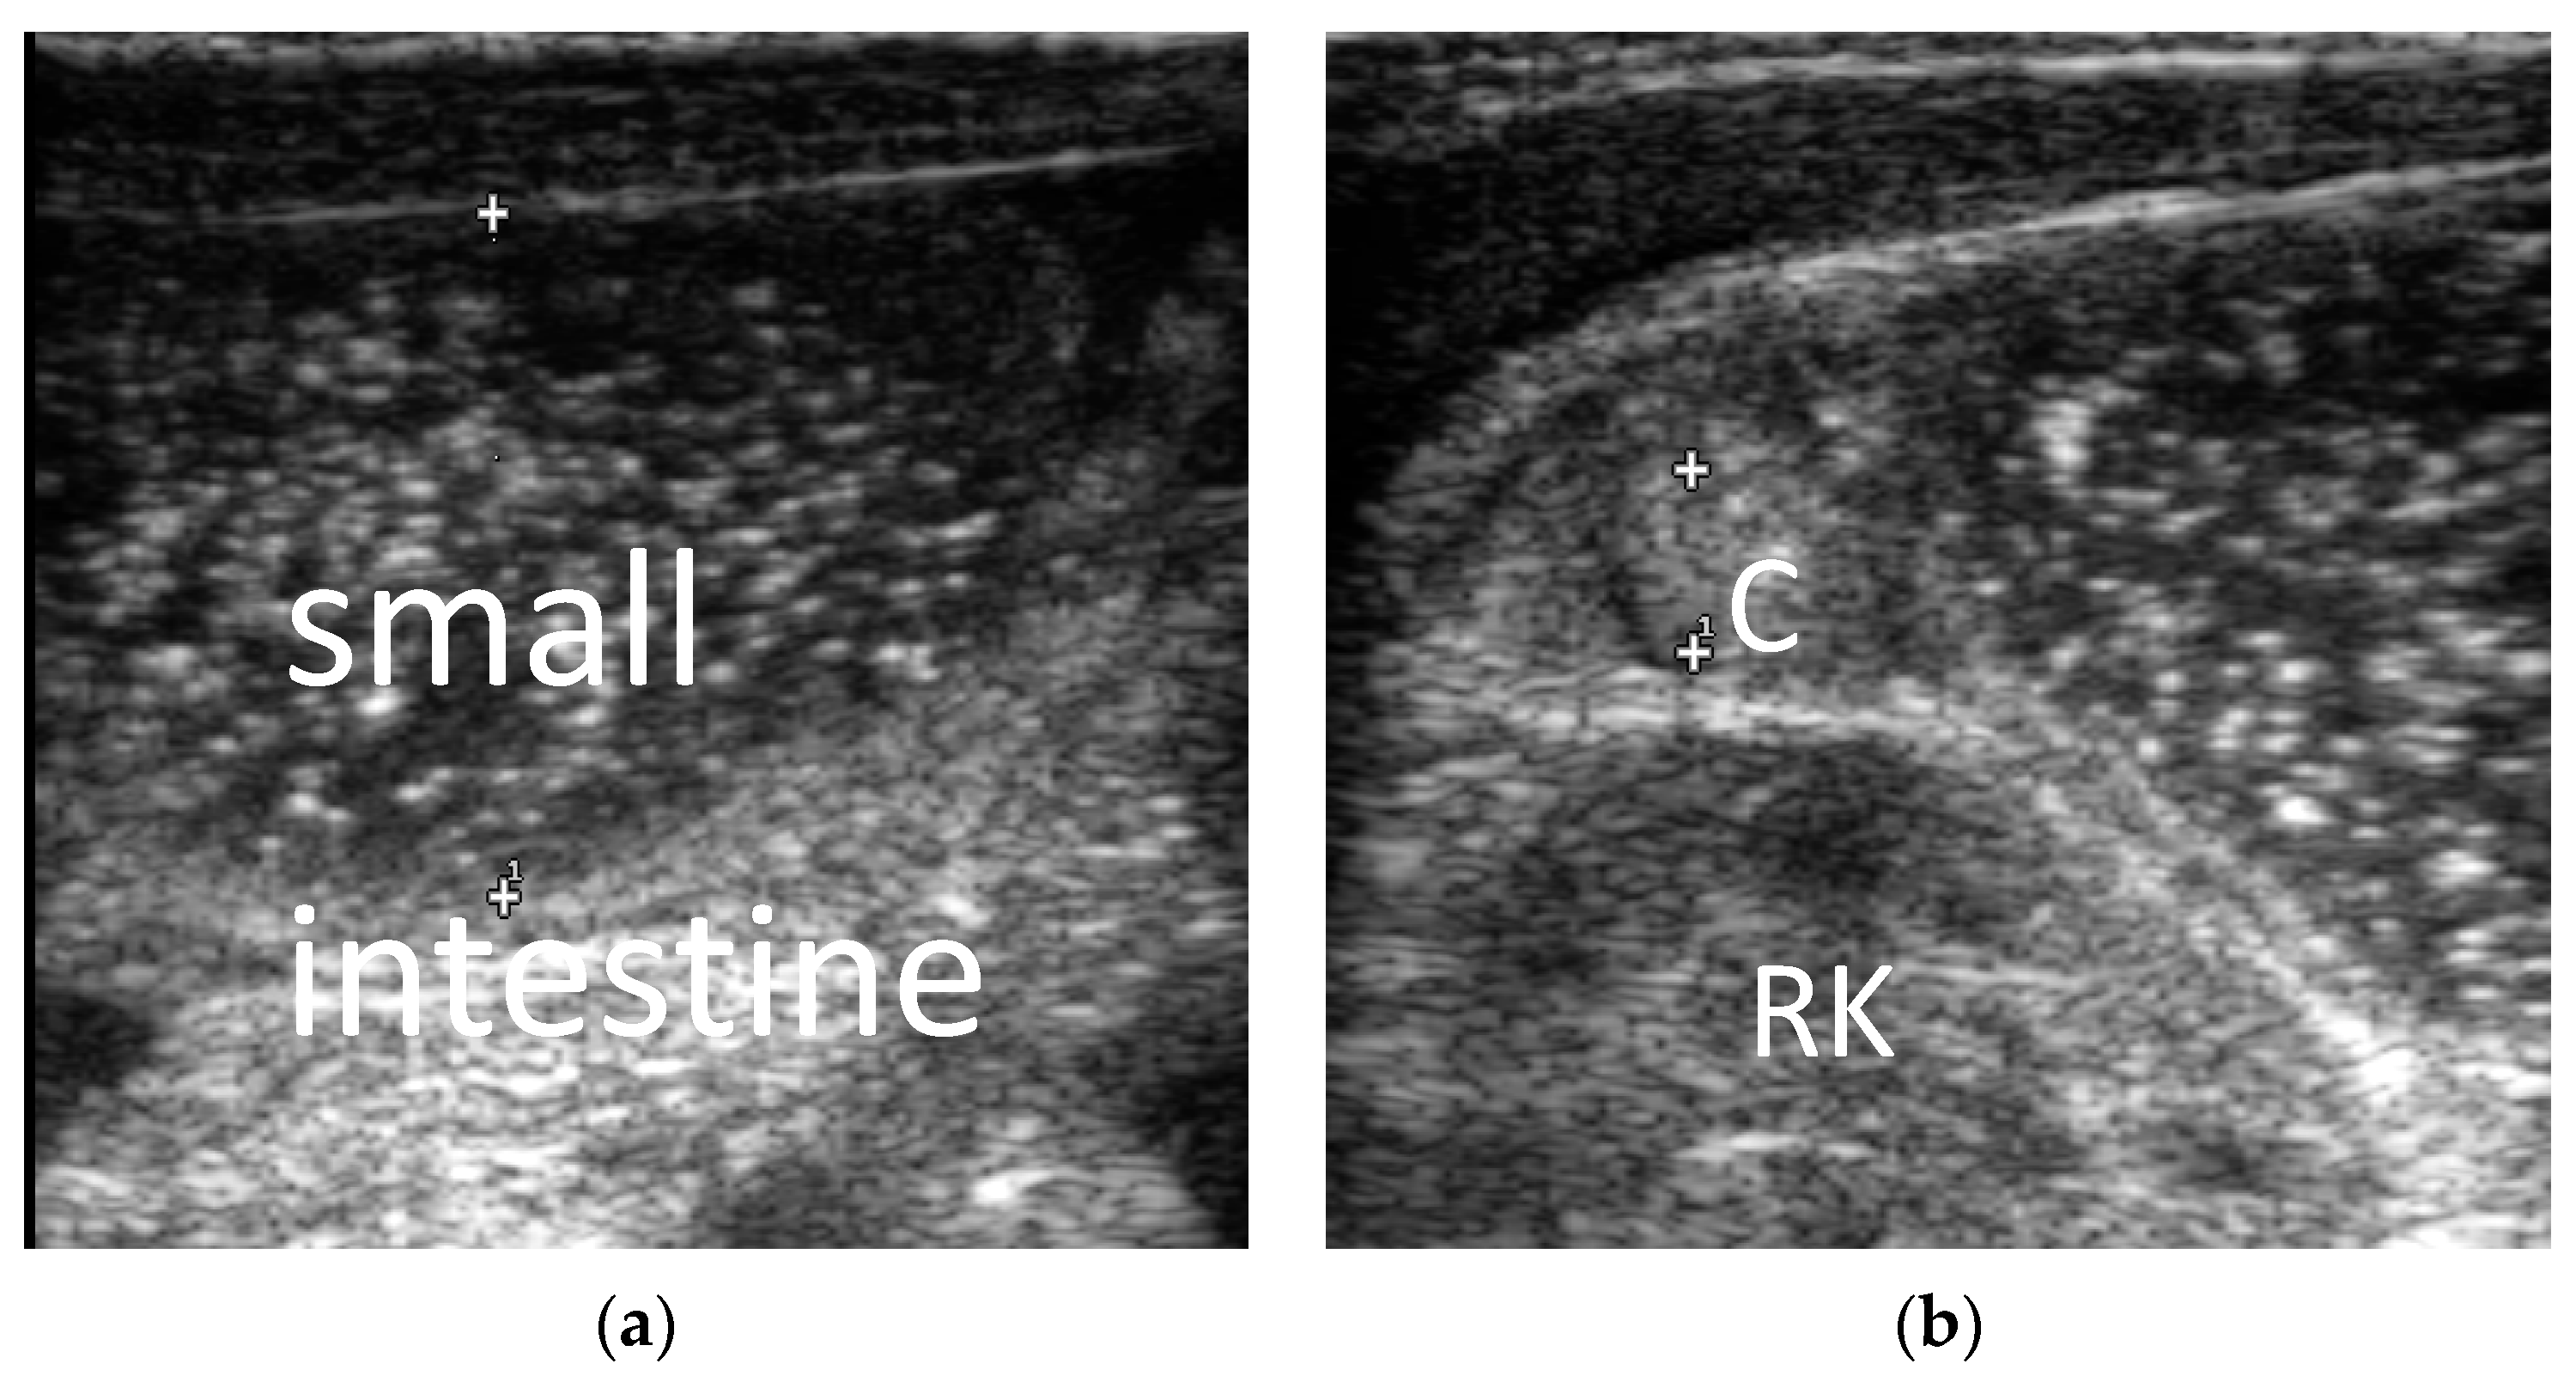

3.2.2. The Corresponding Ultrasound Findings of Diseases Leading to Neonatal Ileus